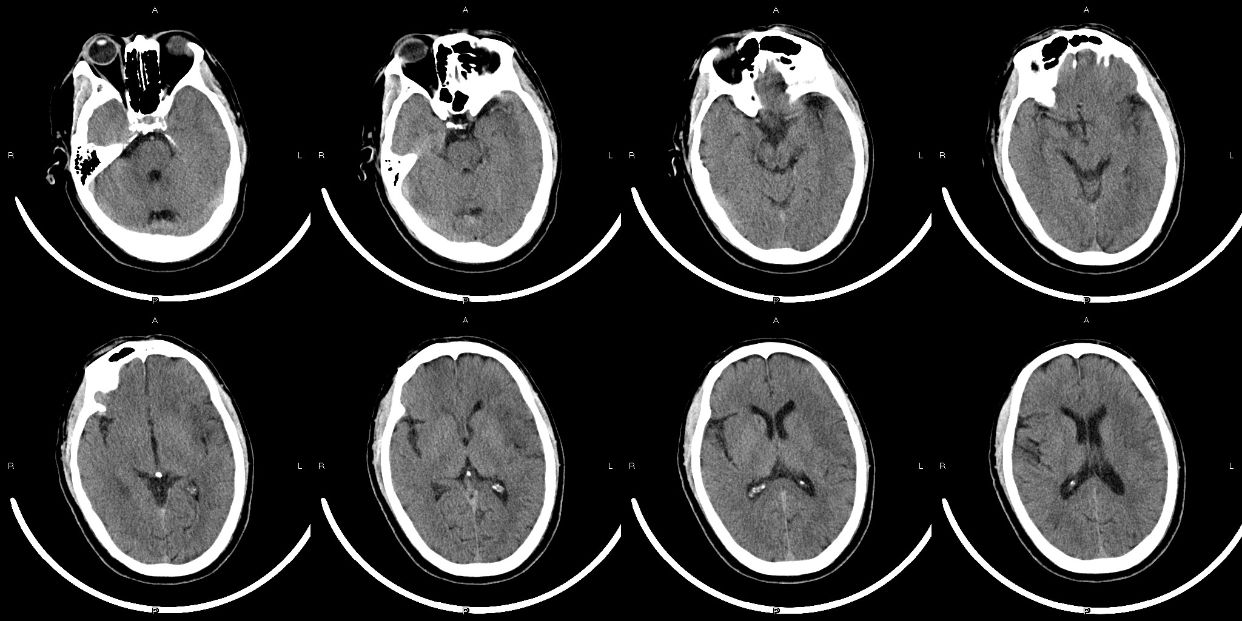

患者信息:男性,58岁,主诉: 突发言语不清伴右侧肢体活动不利8小时转入(在住院期间发病)。

查体: 朦胧,烦躁, 失语,凝视,右侧肢体肌力1级,失语,左侧肢体肌力5级,右侧巴氏征阳性,NHISS 20。

ASPECT评分7分

急性左侧大脑中动脉闭塞,考虑栓塞